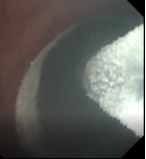

术前支气管 术中改变 术后支气管